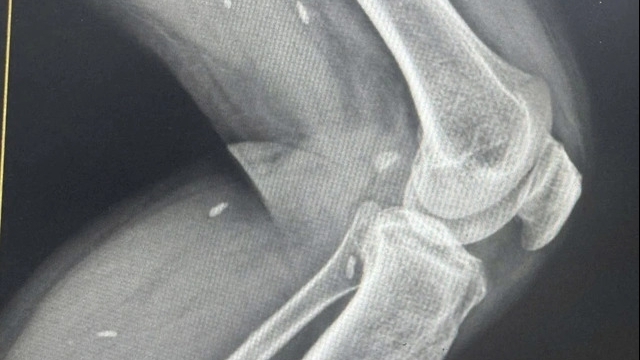

| Hình ảnh điện tâm đồ điển hình của bệnh lý Rung nhĩ kết hợp hội chứng kích thích sớm của bệnh nhân. |

Đó là trường hợp của ông P.V.Đ (ngụ tại Bến Tre) được chuyển đến cấp cứu, điều trị tại Bệnh viện Chợ Rẫy, TPHCM. Ngày 8/7, thông tin từ khoa Điều trị Rối loạn nhịp cho hay, nam bệnh nhân được chuyển đến trong tình trạng rất nguy kịch. Khai thác bệnh sử ghi nhận, nhiều tháng trước người bệnh thường xuyên có các cơn nặng ngực, chóng mặt, hồi hộp dữ dội. Đêm trước khi nhập viện, người bệnh mô tả như tim sắp văng ra khỏi lồng ngực nên cấp tốc đến bệnh viện Nguyễn Đình Chiểu cấp cứu trong đêm.

Tại Bệnh viện Đa khoa Nguyễn Đình Chiểu (Bến Tre) người bệnh trong tình trạng nguy cấp, được các bác sĩ chẩn đoán mắc chứng rung nhĩ nhanh trên nền có bệnh lý kích thích sớm. Đây là một dạng rối loạn nhịp hiếm gặp, nguy cơ đột tử cao nếu rơi vào những cơn nhịp rất nhanh. Theo ghi nhận của bác sĩ, có lúc tim bệnh nhân đập những nhát đến 300 lần một phút (nhịp tim của người bình thường khoảng 60 đến 100 lần mỗi phút).